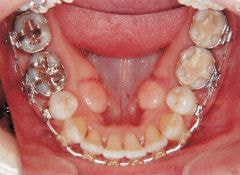

治療例1 (インプラント補綴+矯正)